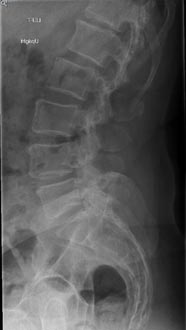

59 year old woman with Scholiosis with severe back pain.

1 year postop from surgery and pain free.